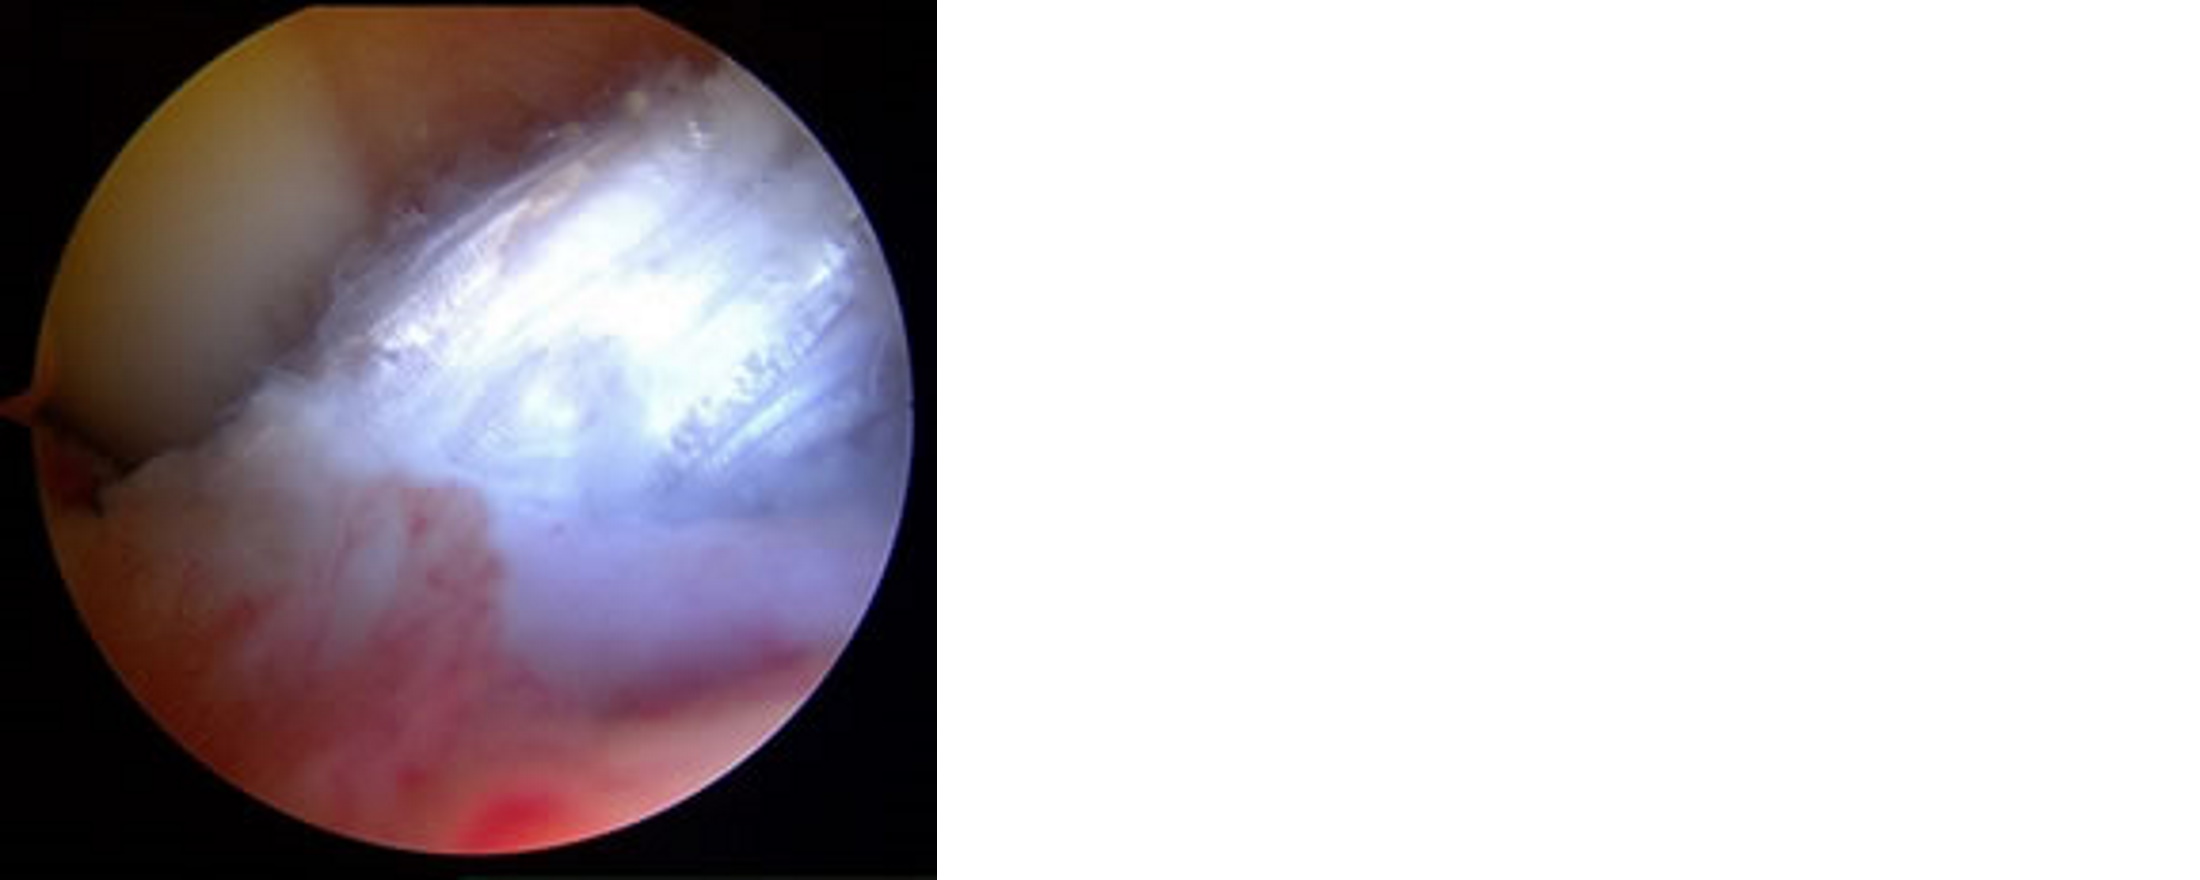

肩関節脱臼は若年者ではスポーツによる受傷が多く、一度でも脱臼すると「肩関節不安定症」という肩が外れやすい状態になってしまいます。繰り返し脱臼するとスポーツなど様々な活動に制限が必要になるばかりでなく、日常生活にも不自由するようになります。脱臼するたびに骨や靭帯を傷めることになるため、できるだけ早期に手術を行って「脱臼しにくい肩」に戻すことが必要になります。当院では10年前から関節鏡を用いた小侵襲の手術を行っています。

棘上筋、棘下筋、小円筋、肩甲下筋という4つの筋の腱が肩関節を覆うように板状になっている部分を腱板と呼び、ここが損傷された状態を腱板損傷といいます。中高年者に多く、特に棘上筋、棘下筋が傷みやすく、手を挙げようと思っても痛みで挙げられなかったりうまく力が入らなくて挙げられないなどの症状が起こります。自然に症状が消失することも少なくありませんが、症状が残る場合には手術を行って損傷した部分を修復する必要があります。当院では10年前から関節鏡を用いた小侵襲の手術を行っています。損傷があまりにも大きい場合には人工関節置換術などの侵襲の大きな手術が必要になることがあります。2014年から日本でもリバース型人工肩関節が認可されました。この手術を行うためには日本整形外科学会が認定する資格が必要ですが、当院でもいち早く資格を取得しています。